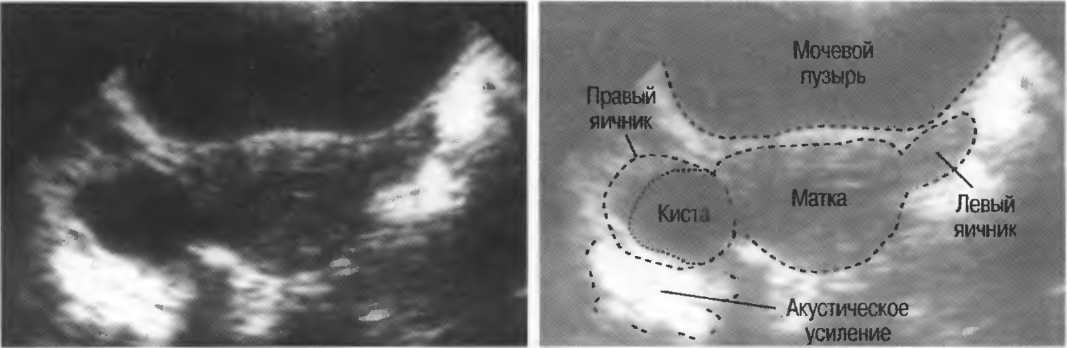

Кисты

Киста, как правило, визуализируется в виде анэхогенной зоны, при этом структуры, расположенные за кистой, обычно усилены: полость кисты анэхогенна, поскольку в ней нет структур с различным акустическим сопротивлением. В результате того что жидкость не поглощает ультразвук в такой же степени, что и ткань, эхо-сигналы от расположенных позади кисты структур гиперкомпенсированы сканером и выглядят усиленными — появляется эффект усиления задней стенки (рис. 14а,б).

Киста определяется в виде анэхогенной зоны с усилением по задней стенке. Если в кисте есть внутренние зхоструктуры, то они могут быть реальными или являться артефактами.

Рис. 14а. Заполненная жидкостью киста: полость кисты анзхогенна, имеется усиление задней стенки.

Рис.14б. Данная киста яичника имеет толстые стенки и внутренний осадок, создающий внутреннюю эхоструктуру, перемещающуюся при перемене положения тела пациента.

Если уровень чувствительности прибора достаточно низок, солидное образование может выглядеть кистозным. Но при этом нет усиления задней стенки (нет дорсального усиления).

Если уровень чувствительности прибора слишком высок, жидкостные структуры могут иметь внутренние зхоструктуры и выглядеть солидными.

Структура, наподобие содержащей чистую жидкость кисты, визуализируется как анэхогенная зона. Стенки кисты отражают ультразвуковые сигналы под углом, и информация не поступает назад в трансдьюсер. В результате этого появляются боковые тени, но сзади кисты имеется усиление эхосигналов (усиление задней стенки) (рис. 15).

Рис. 15а. Киста печени: жидкость внутри чистая, анэхогенная. Стенки кисты отражают ультразвук под углом от датчика, вызывая появление боковых теней.

Рис. 15б. Плодные яйца при анэмбрионии: две жидкостьсодержащие структуры с задним усилением и латеральными тенями.

Артефакты могут определяться в любой кистозной структуре (такой, например, как мочевой пузырь или желчный пузырь) и чаще определяются ближе кпереди, становясь менее выраженными на глубине. Они исчезают или меняют свой характер при изменении положения датчика. Но истинные структуры в кисте, такие как перегородки, сохраняют свое местоположение независимо от положения датчика. Истинные отражения имеют место при наличии сгустка крови, гноя, некротической взвеси, и все это чаще визуализируется по задней стенке: если эти структуры не фиксированы к стенке, они изменяют свое положение при перемене положения тела пациента (рис. 16).

Рис. 16а. Злокачественная киста яичника: крупная киста с внутренней перегородкой, которая остается в прежнем положении при сканировании пациентки в различных положениях.

Осадок в кисте может флотировать, формируя уровень, изменяющий свое положение при перемещении пациента (рис. 16б,в).

Рис. 16б. Киста с усилением по задней стенке, латеральными тенями и осадком в полости.

Рис. 16в. Этот же пациент, что и на рис. 16б. Сканирование осуществляется в разных положениях больного. Уровень, создаваемый осадком, смещается.